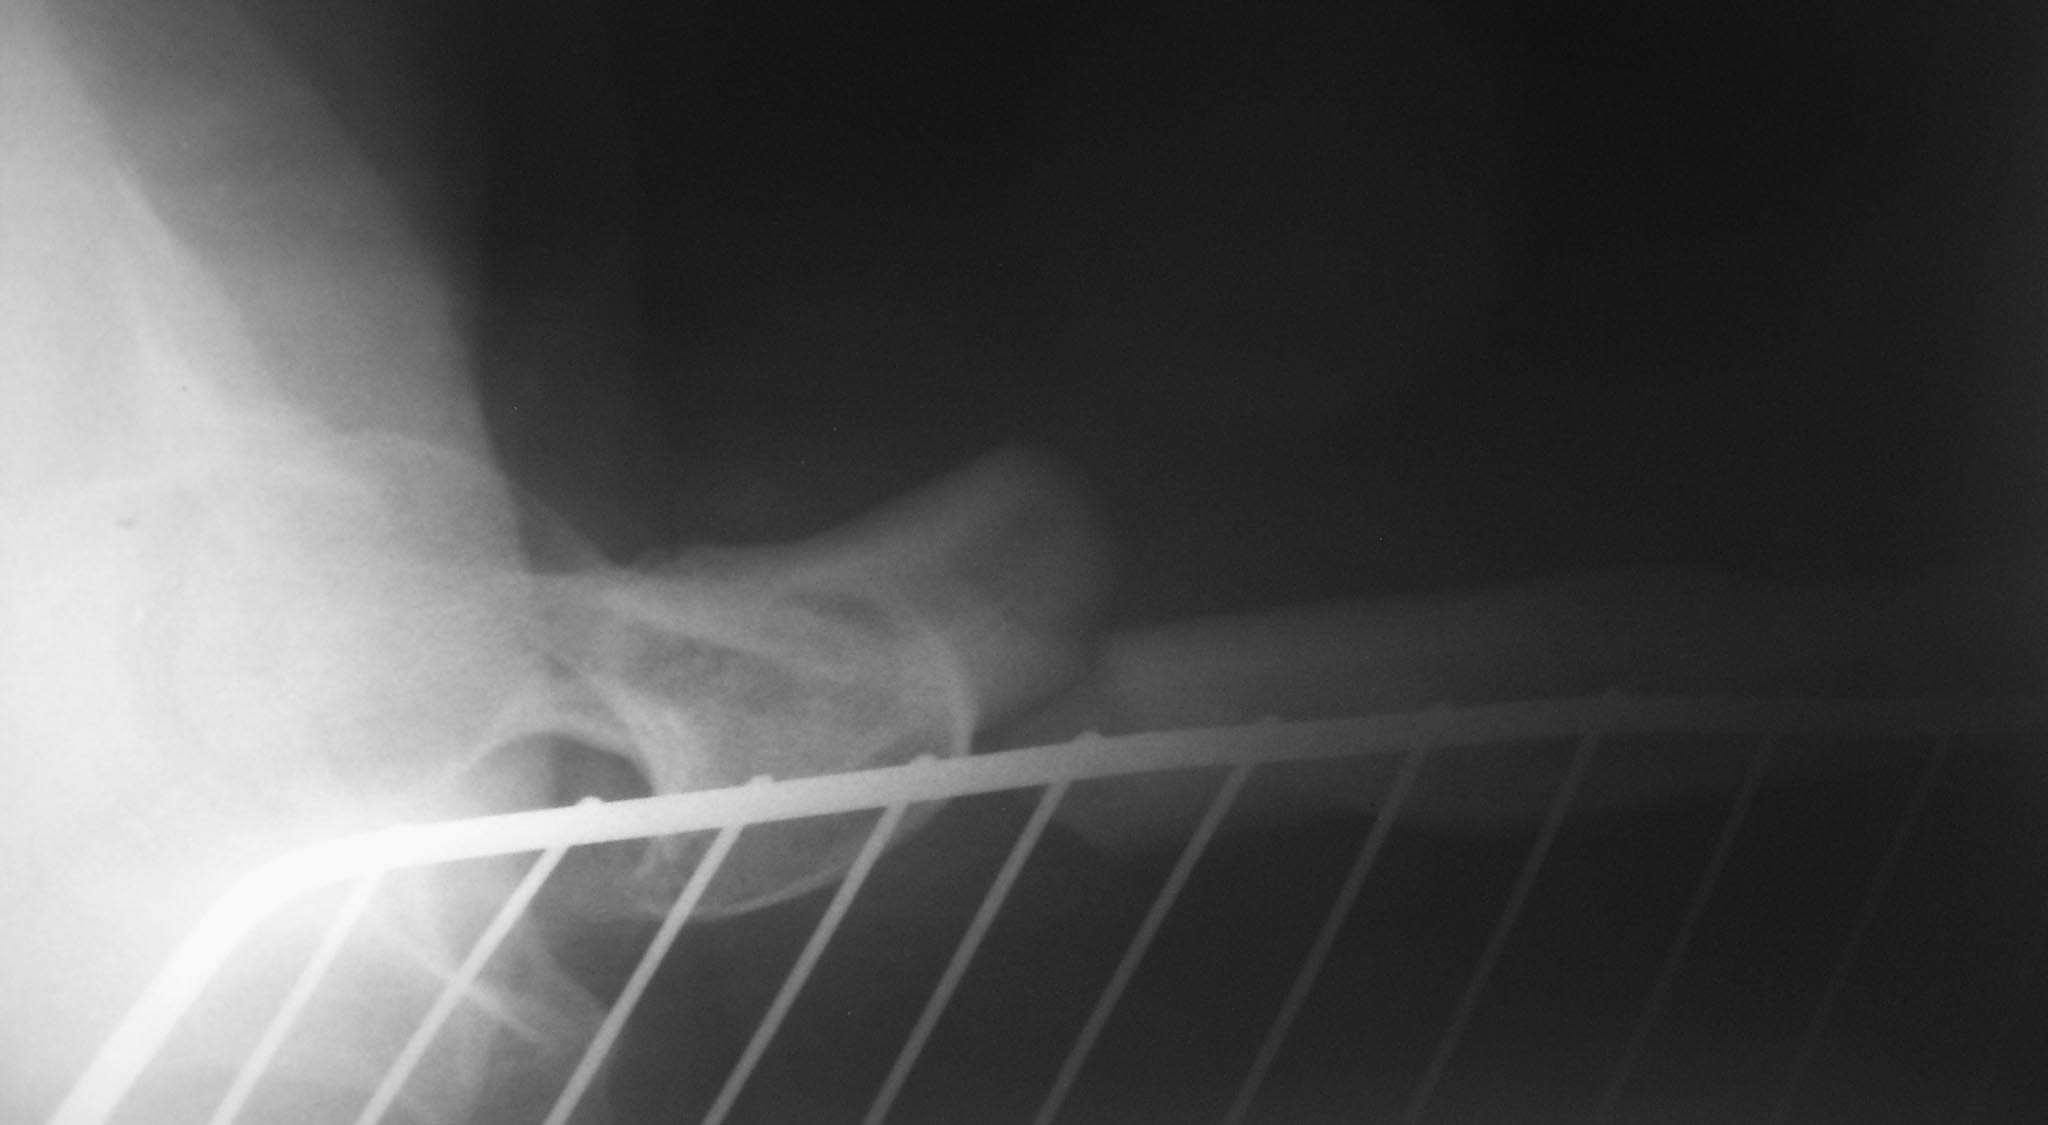

Больная Х, 38 лет. В 3-х летнем возрасте оперирована по поводу врожденного вывиха левого бедра с иммобилизации гипсовой повязкой. Из-за контрактуры коленного сустава разработка на аппарате внешней фиксации Волкова-Оганисяна. В 13-ти летнем возрасте остеосинтез аппаратом Илизарова по поводу перелома бедра. До последней травмы больная работает специалистом отдела кадров. ходила с ортопедической обувью, без вспомогательных средств (трость). Травма ДТП. после травмы мы проводили скелетное вытяжение. После предоперационной подготовки выполнена операция: Закрытая репозиция блокированный синтез левого бедра. компресивным плечевым стержнем №6. т.к подготовленный универсальный стержень для бедра диаметром 8мм не поместился. римерами удалось расширить до 7-го размера.

Уважаемый Асылбек, по представленной рентгенограмме невозможно судить о состоянии тазобедренного сустава. Неясно также на чем основано Ваше суждение об узости и извитости канала бедра. А за счет чего укорочение 7 см? За счет перелома, или до травмы было?

Для такого перелома оптимальным была бы закрытая репозиция и интрамедуллярное шинирование.